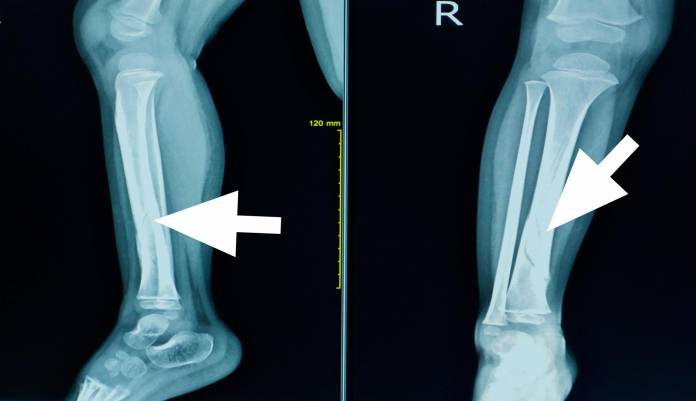

Liegen keine eindeutigen Anzeichen vor, werden weitere Untersuchungen eingeleitet, um die Diagnose zu sichern. Der Arzt wird zunächst den Unfallhergang in Erfahrung bringen und nach einer vorsichtigen Untersuchung des Unterschenkels eine Röntgenaufnahme anordnen. Dieses bildgebende Verfahren zeigt den Knochen und damit einhergehende Frakturen oder Risse sowie Splitterungen.

Mithilfe von Kontrastmittel ist es möglich, im Zuge der Röntgenuntersuchungen Gefäßbeschädigungen festzustellen. Hier kommt aber meist eine Ultraschalluntersuchung zum Einsatz. Auch mithilfe der Computertomographie, auch CT genannt, oder der Kernspintomographie (MRT) lässt sich eine Schienbeinfraktur deutlich erkennen.